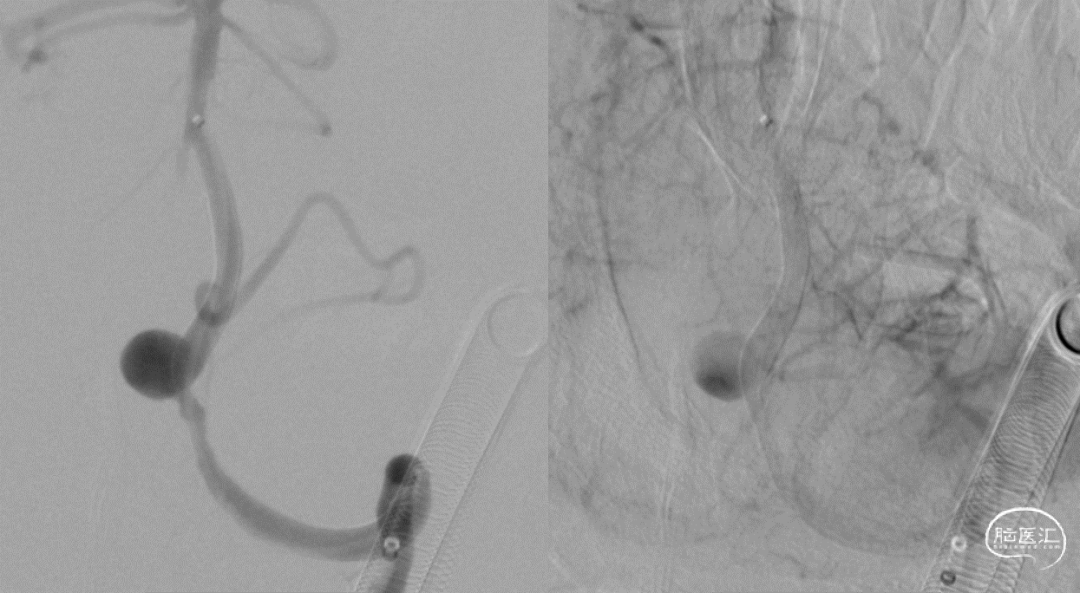

术前造影:

右颈

左椎

6F Navien到位,工作位造影。

Echelon 10微导管预留在动脉瘤瘤腔内,Phenom 27内输送J-Tube™ 4*20血流导向密网支架,顺畅到位,头端打开良好。

J-Tube™打开过程-整体显影性能良好。J-Tube™血流导向密网支架整体释放,贴壁良好。

疏松填塞弹簧圈后正侧位造影。